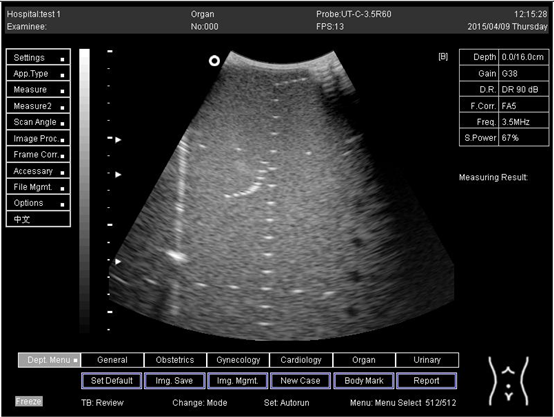

Table A5. The image taken for focal zone determination in different depth for curve probe.

Depth (cm)Diagram

14.0Biomimetics 07 00130 i031

16.0Biomimetics 07 00130 i032

18.0Biomimetics 07 00130 i033

24.0Biomimetics 07 00130 i034